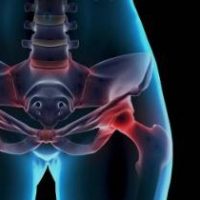

Прилагайки една от най-ефективните терапии за лечение на сухожилия и лигаменти, благодарение на огромния опит и екпертиза на доктор Кавалино ние сме способни да помагаме на хора из цяла България да спрат да чувстват болка.